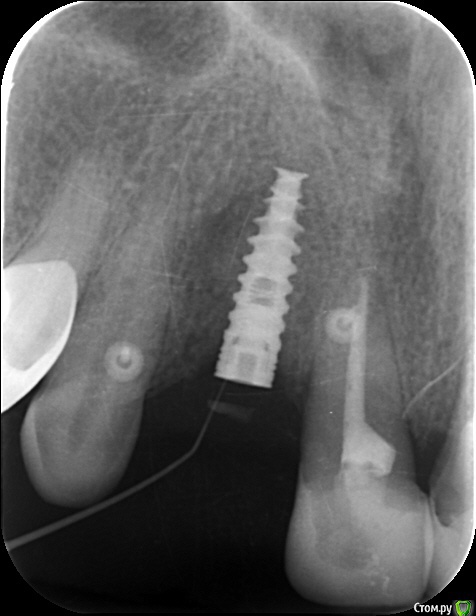

an_ver Опубликовано 12 июня, 2015 Поделиться Опубликовано 12 июня, 2015 История такая.2 месяца назад,поставил SPI 3,75*13 в область ранее удаленного 13 (удалял не я; после удаления прошло 12 недель),щелевидный деффект, торк 25,мр3,эволюшн,небно на шов,вестибулярно на пины. Вчера позвонила,пришла, свищ! Гутту,в заглушку опирается.Закрутить формик? Не рано? По снимкам разница 2 месяца. Ссылка на комментарий

Aquarius Опубликовано 12 июня, 2015 Поделиться Опубликовано 12 июня, 2015 Снимки местами перепутаны? Может просто заглушечный свищ? Открыть, отмыть, ФДМ? 2 Ссылка на комментарий

an_ver Опубликовано 13 июня, 2015 Автор Поделиться Опубликовано 13 июня, 2015 Снимки местами перепутаны? Может просто заглушечный свищ? Открыть, отмыть, ФДМ?Перепутаны. Ссылка на комментарий

ILGAMSA Опубликовано 13 июня, 2015 Поделиться Опубликовано 13 июня, 2015 Пины тоже удалить при установке формика?Андрей, ставьте формирователь. Имплант уже интегрирован. Если пины в зоне интереса, то можно убрать. Если нет, то не надо. 2 Ссылка на комментарий

an_ver Опубликовано 15 июня, 2015 Автор Поделиться Опубликовано 15 июня, 2015 Проблема была не в заглушке. Обратите внимание на светлую полосу над заглушкой.Кусок косточки(((,раскрыл,промыл,формирователь. 1 Ссылка на комментарий